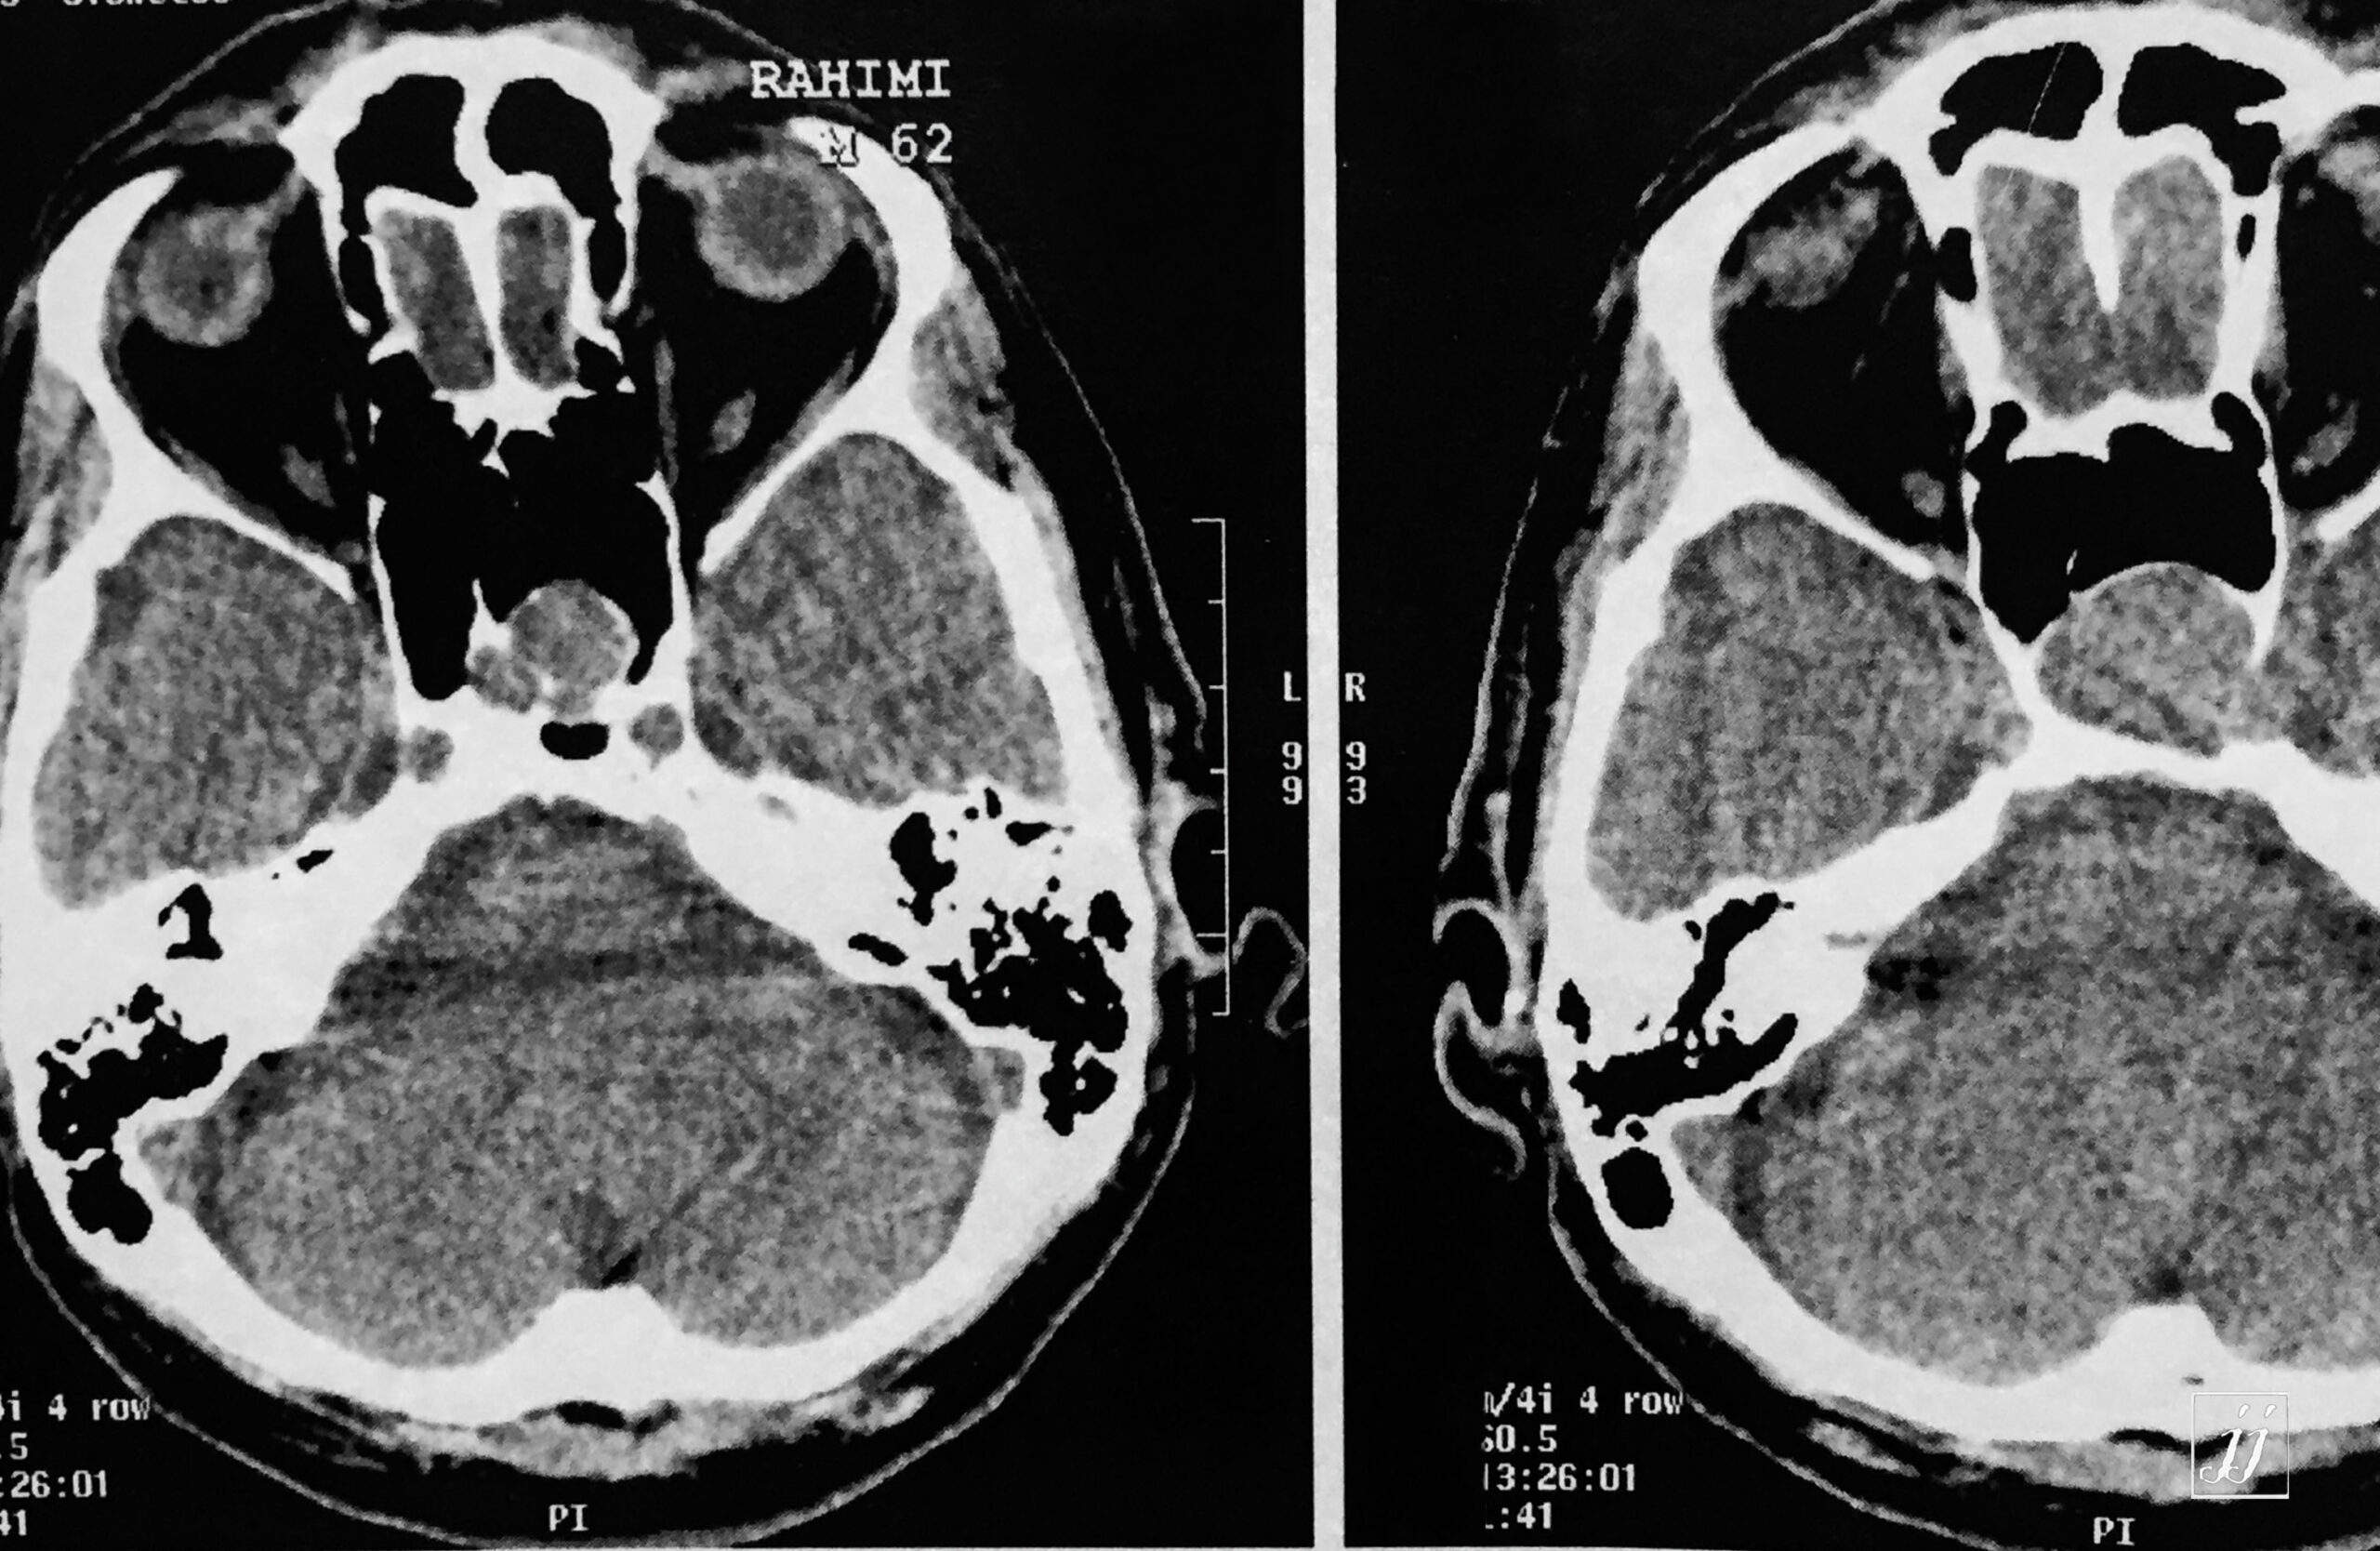

Brain- Hypophysis pituitary macro adenoma (3)